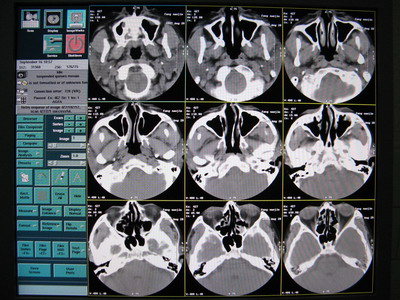

6.原因會(huì)不會(huì)是數(shù)據(jù)到了 OC 這邊重建出了問(wèn)題呢,用原來(lái)正常圖像的原始數(shù)據(jù)用相同的條件進(jìn)行重建,發(fā)現(xiàn)正常圖像的原始數(shù)據(jù)重建出來(lái)的圖像出現(xiàn)了偽影,如下圖:

正常的圖像

重建出來(lái)的偽影圖像

7.用原來(lái)掃出來(lái)不正常空氣圖像的原始數(shù)據(jù)用相同條件反復(fù)重建如下圖:

從上面幾幅圖可以看出,每次重建出來(lái)圖像出現(xiàn)偽影的地方都不同,原來(lái)不正常的圖像可以重建出正常的圖像,再次證明了原始數(shù)據(jù)是沒(méi)有問(wèn)題的。